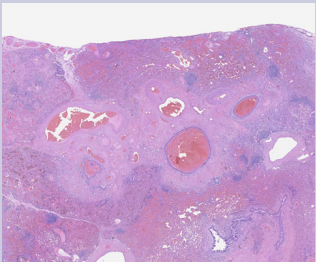

The most prominent hemosiderin deposition was seen in a portion of lung that contained an abnormal collection of small arteries and veins with associated fibrosis that forms a vascular tangle. This vascular tangle was located at the periphery of the lung near the pleural surface and surrounds a broncho-vascular structure that displays traction bronchiectasis [Figure 4 & 6].

Figure 4: An abnormal collection of blood vessels with various sizes in the subpleural lung parenchyma (20x). Prominent collections of hemorrhage are seen in surrounding alveolar airspaces and distended bronchioles.

Figure 6: This abnormal vascular tangle contained mostly small veins and venules with a few small arteries and arterioles (20x). The lack of associated airways with some of the small arteries and arterioles also suggested an abnormal vascular malformation. Classic features of arteriovenous malformation were not identified

Some of the vessels showed evidence of prior thrombosis with multiple recanalized lumens. A few of the vessels had changes, that represent several episodes of recurrent thrombosis and recanalization [Figure 4 & 6]. Some of these vessels showed abnormal aneurysmal dilatation. These findings were most suggestive of a vascular malformation and not normal lung as they lack the associated airways. Focally, the pleural surface adjacent to this malformation showed an increased numbers of variably sized arteries and veins, which may be part of the same process [ Figure 4 & 6].